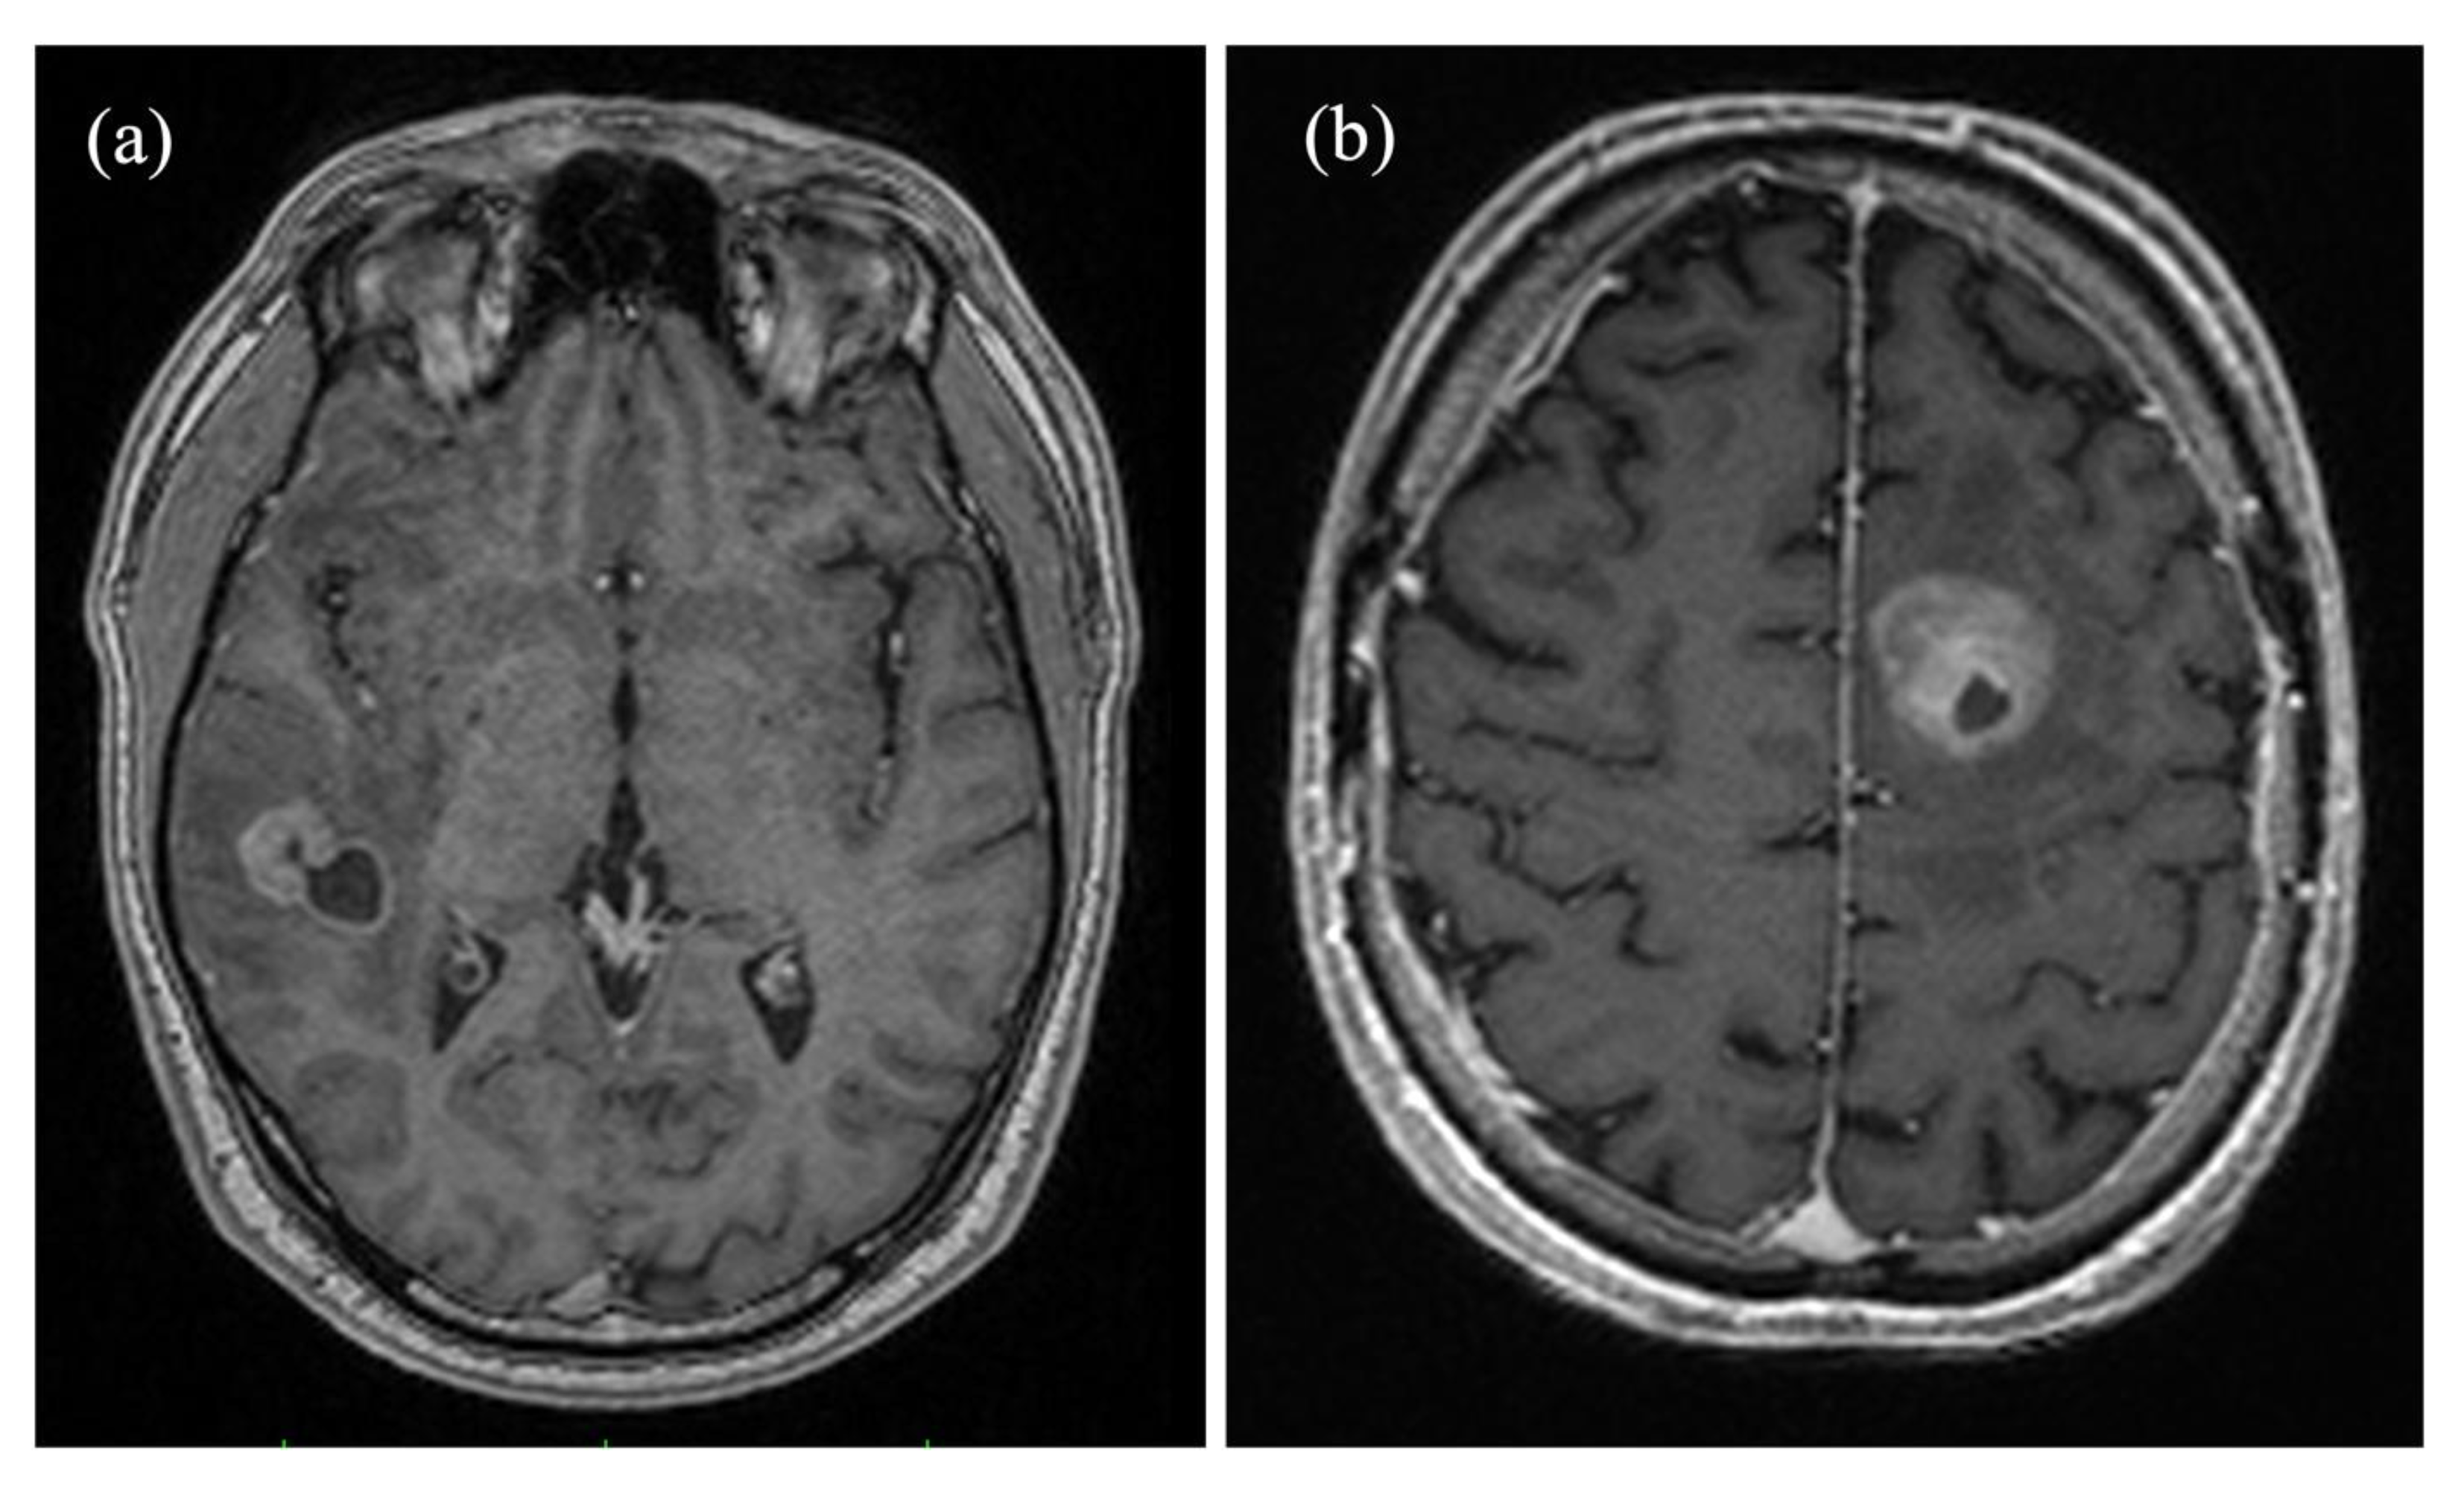

2.1. Patients

2.2. Image Acquisition

2.3. Image Processing